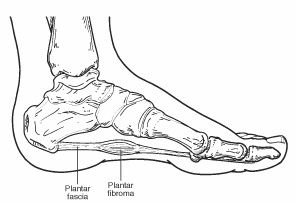

A plantar fibroma is a fibrous knot (nodule) in the arch of the foot. It is embedded within the plantar fascia, a band of tissue that extends from the heel to the toes on the bottom of the foot. A plantar fibroma can develop in one or both feet, is benign (non-malignant), and usually will not go away or get smaller without treatment. Definitive causes for this condition have not been clearly identified.

The characteristic sign of a plantar fibroma is a noticeable lump in the arch that feels firm to the touch. This mass can remain the same size or get larger over time, or additional fibromas may develop.